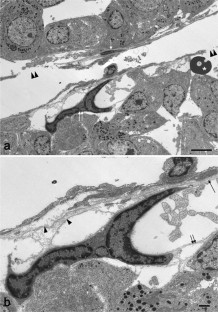

Prolactinomas are the most common tumor of the human pituitary. They result in excessive prolactin secretion and important changes in the vasculature. Pericytes are perivascular cells associated with capillaries and have crucial roles in physiological and pathological neovascularization. We previously reported that pericytes produce type I and III collagens in the anterior pituitary of adult rats. In addition, pituitary pericytes contained well-developed cell organelles and actively synthesized collagens during early postnatal development. However, the characteristics of pericytes in pituitary tumors are unclear. In this study, we used diethylstilbestrol (DES)-treated rats as an animal model of prolactinoma. Using five common pericyte markers, more pericytes were observed in rats treated with DES for 3 months (prolactinoma) compared to the control. Transmission electron microscopy revealed that attached and semidetached pericytes exhibited active cell organelles. Moreover, we identified pericyte migration between capillaries. Although the fine structure of pituitary pericytes was active in prolactinoma, expressions of type I and III collagen mRNAs were greatly diminished. In sum, the characteristics and functions of pericytes were altered in pituitary tumors. This study is the first to clarify fine structural changes of pericytes in rat prolactinomas and improves our understanding of the function of pericytes under pathological conditions.

Fig. 2